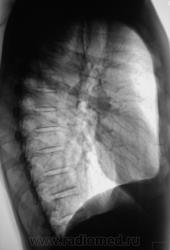

Первое исследование.